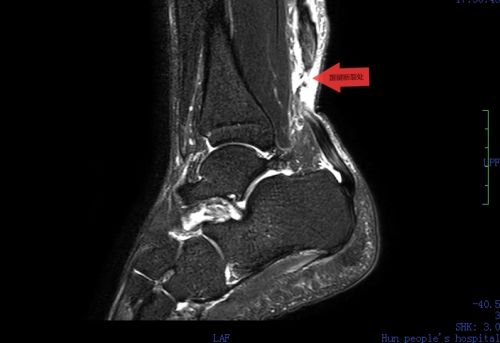

mri显示,右足跟腱距跟骨附着点68mm处断裂,断端分离约8mm。